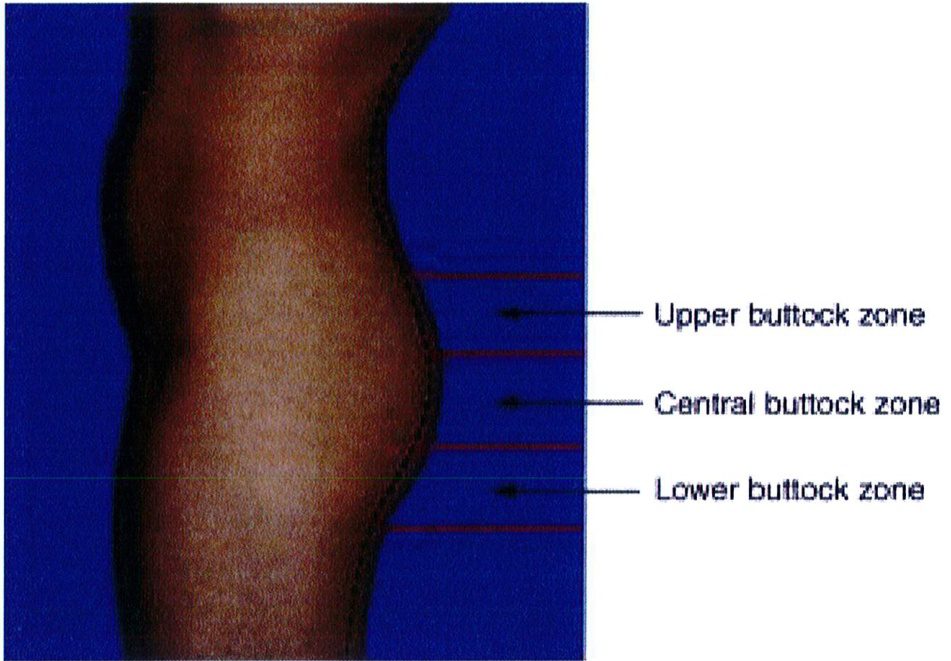

Mặt bên vùng mông có thế được chia thành 3 vùng: trên, giữa, dưới (xem hình 19). Sự phân chia tương ứng với 3 điểm A, B, C và chúng giúp xác định vùng nào được phân bố mỡ nhiều/ít hơn các vùng còn lại. Trong thấm mỹ vùng mông, phần lớn mô mỡ dưới da sẽ nằm ở vùng trung tâm (chính giữa mông), và phần mỡ dưới da còn lại sẽ được phân bố đồng đều ở hai bên. Như vậy chúng ta có thể tưởng tượng ra hình dạng tổng thể của mông khi nhìn từ phía bên là hính chữ C ngược (Hình 19). Có một số tác giả cho rằng điểm nhô ra nhiều nhất của vùng mông sẽ là điểm nằm ngang với xương mu ở tư thế đứng.

Khi làm việc từ góc nhìn bên này, chúng ta cần rõ ràng xác định được đâu là ranh giới vùng mông trên giữa dưới (Hình 20). Việc xác định này rất quan trọng nhằm

Hình. 19. Ba vùng trên giữa dưới của mông.

Hình. 20. Phần lớn thể tích vùng mông tập trung ở 1/3 dưới, giữa, trên.